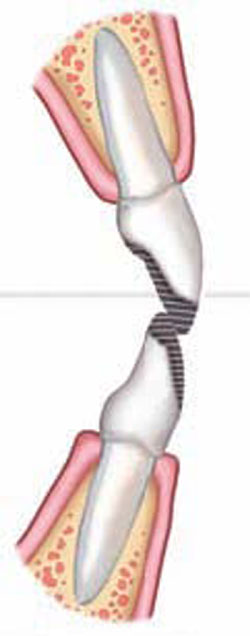

Perhaps one of the most common yet complex cases involves severe wear of the incisal edges of anterior teeth. When a parafunctional habit exists,4 incisal wear develops to varying degrees depending on the malocclusion (Figure 1A) and the patient’s age. Accompanying the wear is the often underappreciated dentoalveolar extrusion of the teeth,5 resulting in short and unesthetic anterior teeth with irregular gingival margins (Figure 1B). Often, these cases are treated by crown lengthening and restoration only, which is a compromised treatment plan. It requires unnecessary removal of vital soft and hard tissue and creates greater risks of damage to the pulpal tissues during final preparations.6 However, treating the fundamental problems requires the orthodontic intrusion5 of the anterior dentogingival complex (Figure 1C) and subsequent restoration of the lost tooth structure5 (Figure 1D). Leveling the gingiva can serve as an initial guide7 for the orthodontist. However, until the correct incisal edges are in place, he or she cannot accurately predict how the teeth relate to the lips when smiling, nor how the tooth form relates to the envelope of function4 as orthodontics is finalized (Figure 1E). In addition, the patient may not appreciate the unsightly “disappearance” of the remaining tooth structure, if teeth are intruded significantly during the orthodontic process (Figure 1C). Options for addressing these problems include preparation of the teeth and placement of provisional crowns (represents aggressive therapy and is prone to maintenance problems); composite-resin bonding (a very conservative treatment);8 or no restorative treatment at this stage. Because bonded-porcelain restorations preserve more tooth structure as compared with conventional metal-ceramic crowns, they are preferred as final restorations in most cases; therefore, conservation of tooth structure at this stage is most desirable.6

Adding the incisal edges in composite resin during orthodontic treatment seems an obvious and proven solution. This form of “trial therapy”4 is traditionally performed with the brackets in place and the wire removed by the “free-hand” placement of composite resin. Likely reasons that this is not more common may be ascribed to the level of difficulty involved and the amount of time required in placing direct composites in the esthetic zone. Also, the dentist may hesitate to increase costs to the patient who is already anticipating a substantial investment in final restoration. A simpler and less time-consuming method can be employed in which a wax-up is performed on a diagnostic model1 and a clear vinyl polysiloxane (VPS) matrix is used to direct warmed composite resin onto the teeth.9 The latter method serves well by reducing chair-time for the dentist and lowering cost to the patient; and the immediate improvement in the smile can be dramatic. In the authors’ experience, patient responses have been overwhelmingly positive. The orthodontist or restorative dentist can make modifications as needed to satisfy the esthetic or functional requirements of the case with the patient’s approval as final orthodontic movements are performed (Figure 1E).

Final porcelain restorations are placed only after adequate time has elapsed to allow settling of the teeth following bracket removal and healing of the gingival tissues. Intrusion cases may require up to 6 months of retention to achieve stable positions,7 and soft-tissue maturation may require an even greater length of time. The intermediate composite-resin restorations serve as the template for the final porcelain restorations, establishing proper incisal-edge position, emergence form, and functional occlusion,4 while maintaining optimal gingival health and esthetics. Ideal preparations can now be made with maximal conservation of tooth structure in mind to help ensure the longevity of the final restorations.6

Figure 1A Unwom initial malocclusion |  Figure 1B Dental wear with secondary dentoalveolar extrusion | ||||||

Figure 1C Orthodontic overcorrection |  Figure 1D Intermediate restoration to ideal anatomy (not function) | ||||||

Figure 1E Orthodontic finalization of esthetics and function | |||||||

| FIGURE 1A THROUGH FIGURE 1E Incisal wear with dentoalveolar extrusion. Note the relationship of the maxillary incisal edge to lip line. | |||||||